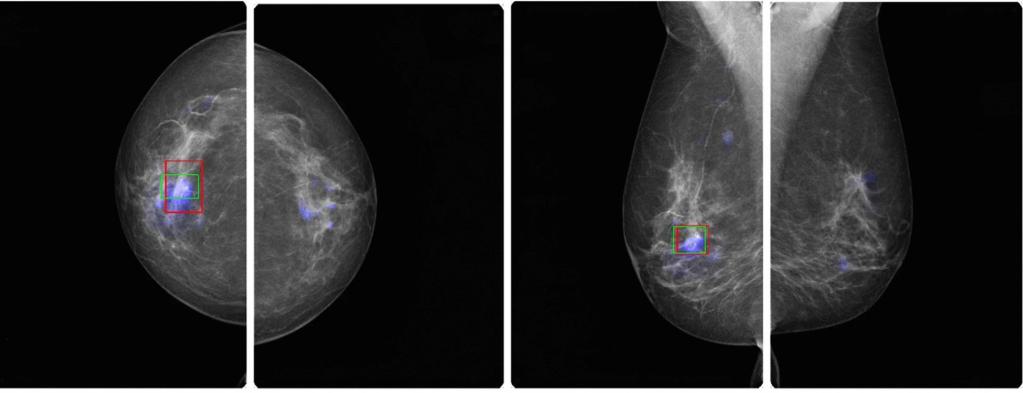

Einsatz von künstlicher Intelligenz

Hier kommt im Radiologischen Zentrum nun neuerdings künstliche Intelligenz zum Einsatz. Nach dem Motto "Vier Augen sehen mehr als zwei" werden die Aufnahmen auch von einer künstlichen Intelligenz beurteilt und dabei erkannte auffällige Befunde werden kenntlich gemacht. Letztlich entscheidet aber die Radiologin oder der Radiologe, die/der weitere Informationen aus der Vorgeschichte, den Tastbefund und die Ultraschalluntersuchung einbeziehen kann.

Wissenschaftliche Studien haben aber gezeigt, dass mit diesem Prinzip der KI-Zweitbefundung weniger krankhafte Befunde übersehen werden.

KI Software

Die von uns verwendete KI Software stammt von der Schweizer Firma b-rayZ AG. Sie wurde an tausenden von Mammographien mit gesicherten Befunden "angelernt" (Machine Learning). Die Software wird im Rahmen des Qualitätsprogramms QuaMaDi eingesetzt, kommt aber bei uns auch Patientinnen zugute, die nicht an QuaMaDi teilnehmen (können).